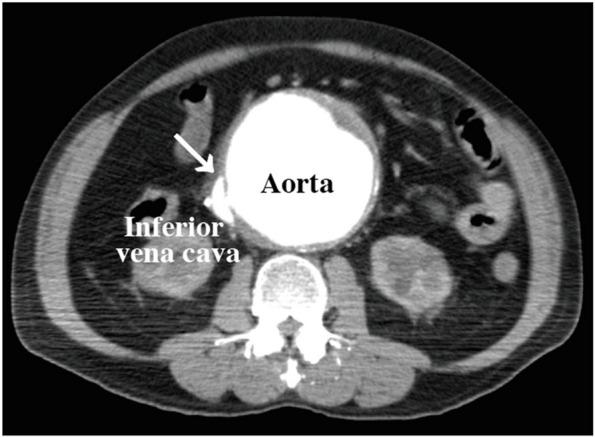

CASE PRESENTATION

A 71-year-old man with a history of atrial fibrillation and catheter ablation presented with heart failure and abdominal pain, leading to cardiac arrest. Imaging revealed an AAA rupture into the inferior vena cava. During emergency surgery, severe venous bleeding was managed using intra-aortic balloon occlusion (IABO). Transesophageal echocardiography (TEE) identified a right-to-left shunt due to an iatrogenic atrial septal defect.

一名71岁有房颤和导管消融病史的男性患者,因心力衰竭和腹痛就诊,随后发生心脏骤停。影像学检查显示腹主动脉瘤破裂至下腔静脉。在急诊手术期间,采用主动脉内球囊阻塞(IABO)处理严重的静脉出血。经食管超声心动图(TEE)发现因医源性房间隔缺损导致右向左分流。